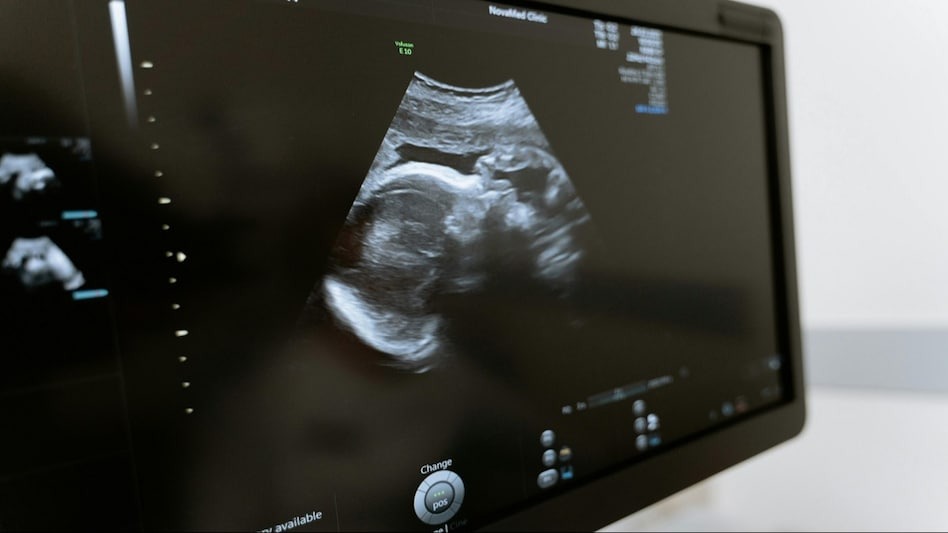

रिपोर्टका अनुसार ड्यानिएला भेरा नामकी ८१ वर्षीया महिला निकै अनौठो अवस्थाबाट पीडित थिइन् । एक्कासी पेट दुखेपछि डाक्टरकहाँ जाँदा उनको पेटमा क्याल्सिफाइड भ्रूण रहेको थाहा भयो ।

ड्यानिएलाको उपचार गर्ने डाक्टर प्याट्रिक डेजिरेमले शल्यक्रियापछि संक्रमणका कारण महिलाको मृत्यु भएको खुलासा गरेका छन् । उनले भनेअनुसार कतिपय अवस्थामा पाठेघरको सट्टा शरीरको अन्य भागमा गर्भधारण हुने गरेकोले यसलाई एक्टोपिक प्रेग्नेन्सी भनिन्छ ।

यो एक प्रकारको गर्भावस्था हो जहाँ निषेचित अण्डा गर्भाशय बाहिर गर्भधारण गर्दछ, जहाँ यो बाँच्न सक्षम छैन। डेनियलसँग पनि यस्तै भएको थियो । बच्चाको विकास राम्रोसँग नभएको कारणले गर्दा यो क्याल्सिफाइड हुन्छ। यस्तो अवस्थामा शरीरमा न त कडा पीडा हुन्छ न रगत बग्ने हुन्छ । एक्सरे नगर्दासम्म शरीरमा कुनै लक्षण देखिँदैन।